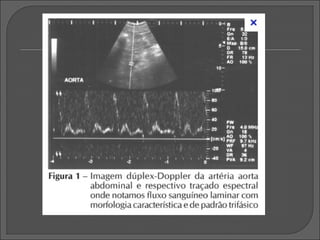

INTERPRETAÇÃO DO SINALDOPPLER Espectro Normal  Na onda de velocidade de fluxo há um período sistólico e diastólico.  Sistólico – o fluxo é laminar e as velocidades das hemáceas são semelhantes. Qdo ordenadas no espectro da onda de fluxo normal essas frequências deixam uma janela na fase sistólica.  Diastólica – cessa o fluxo laminar , desaparecendo a janela.